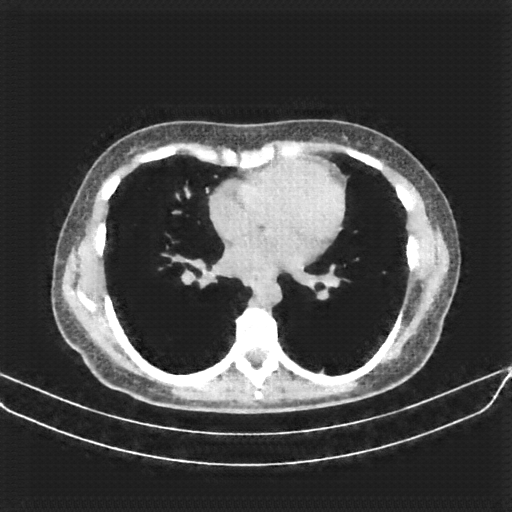

Image Grid

4Γ—3 grid: Rows show different image types (Original NATIVE, Reconstructed NATIVE, Original VENOUS, Generated VENOUS), Columns show windowing techniques (No Window, Lung Window, Mediastinum Window)

Original NATIVE CT scan (input)

Lung window (WL -600, WW 1500 β†’ Low βˆ’1350, High +150)

Original VENOUS CT scan